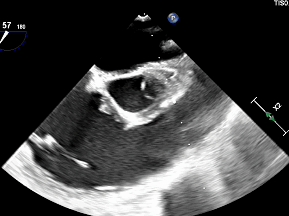

出院前超声

心脏位于左侧胸腔,心尖指向左下。房室连接正常。右心较术前减小。左室壁不增厚,运动未见明显异常。主动脉瓣形态结构未见异常;二尖瓣形态结构未见异常;三尖瓣形态结构未见异常。

CDFI:AR(-),MR(少量),TR(少量)。房间隔中部探及两处封堵器回声,房水平未见明显分流。室间隔连续完整,室水平未见明显分流。肺动脉内径不增宽。升主动脉内径23mm。心包腔内未见明显液性暗区。